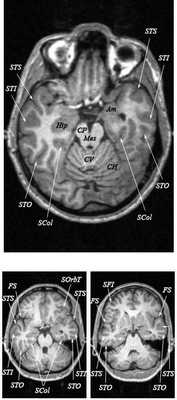

МРТ головного мозга. Т2-взвешенная аксиальная МРТ. Цветовая обработка изображения.

Знание анатомии мозга очень важно для правильной локализации патологических процессов. Ещё более важно оно для изучения самого мозга с помощью современных «функциональных» методов, таких как функциональная магнитно-резонансная томография (fMRI), и позитронно-эмиссионная томография. С анатомией мозга мы знакомимся ещё со студенческой скамьи и существует множество анатомических атласов, в том числе и поперечных сечений. Казалось бы, зачем ещё один? На самом деле, сравнение МРТ срезов с анатомическими приводит к множеству ошибок. Это связано как со специфическими особенностями получения МРТ изображений, так и с тем, что строение мозга очень индивидуально.

Представленная страница сайта основана на специальном изучении МРТ головного мозга здоровых лиц. Для этого изображения получали с минимальной величиной воксела (1 мм в каждом измерении), что исключало наслоения борозд. Каждая из структур прослеживалась в трёх реконструированных плоскостях путём её выделения с помощью компьютерной программы. Мы рассматривали различные анатомические варианты, что обсуждается в работе. В результате, учитывая вариабельность строения мозга, подобран условно «стандартный» мозг. Поскольку на сайте нереально представить 128 срезов в каждой из основных плоскостей, мы ограничились только каждым пятым срезом. Основные срезы в поперечной плоскости даны без наклона назад (угол 0º). Под ними для представления о изменении соотношения анатомических структур демонстрируются срезы, выполненные на тех же уровнях, но с наклонами назад -15º и -30º.

Поперечные (аксиальные) МРТ срезы головного мозга